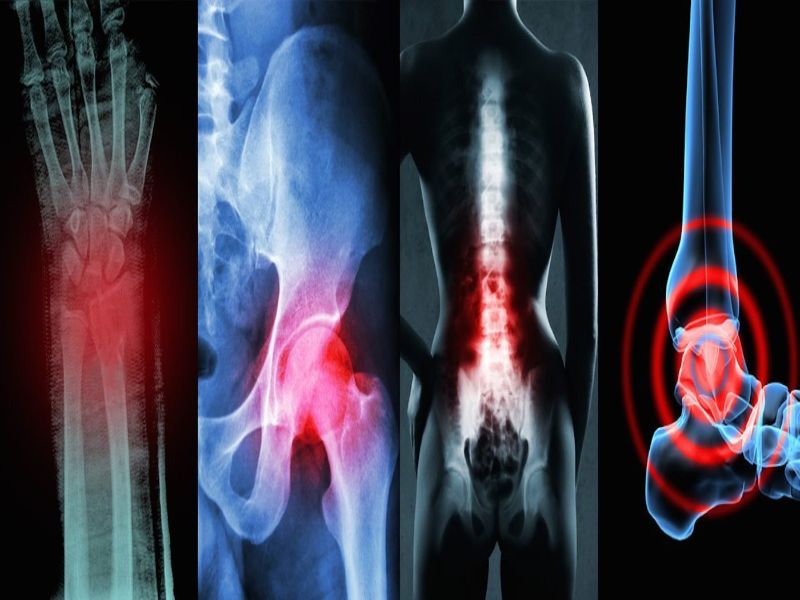

Cuando algunos de estos cartílagos sufren alguna lesión, se genera dolor, rigidez y sobre todo incapacidad funcional. Comúnmente la artrosis se encuentra en la columna cervical y lumbar de los seres humanos, algunas de las veces también se pueden localizar en los hombros y los dedos de las manos. En las caderas, rodillas y rara vez en la articulación del dedo gordo del pie.

La artrosis en las caderas se refiere al desgaste de los cartílagos de esta articulación. Este tipo de enfermedad es muy frecuente, pero no tanto como la de rodilla o de las manos. Esta puede aparecer en las personas antes de los 50 años de edad. Uno de los síntomas es el dolor, aunque también puede aparecer rigidez y deterioro de la movilidad de la misma. El dolor de este tipo de artrosis se localiza en la ingle.

Este tipo de artrosis se produce cuando las personas sufren alguna lesión o degenera el cartílago de todas las articulaciones de la columna cervical. Este tipo de enfermedad es muy frecuente en las personas mayores de 50 años de edad. Uno de los síntomas más comunes es el dolor del cuello, que se puede detectar con los movimientos.

- Artrosis lumbares

Este tipo de enfermedad se produce cuando se sufre una lesión o se desgasta el cartílago de las articulaciones de la columna lumbar. Esta está compuesta por cincos vértebras que están localizada en la espalda, entre las costillas y la pelvis. Los síntomas más comunes para detectar este tipo de artrosis son el dolor, la rigidez y la poca limitación para realizar cualquier movimiento.

- Artrosis de mano

Se produce por los desgastes de los cartílagos de las articulaciones de las manos. Esta suele generar mucho dolor, rigidez y dificultad a la hora de realizar movimiento en los dedos. Este tipo de enfermedad generalmente comienza entre los 40 y 50 años, siendo más frecuente en mujeres, aunque este tipo de artrosis puede presentarse en ambos sexos.

- Artrosis de rodilla

Las articulaciones de las rodillas la conforman el fémur, la tibia y el peroné. Este tipo de artrosis se caracteriza por el deterioro que genera el cartílago, provocando que se genere dolor con la actividad física, problemas para caminar y permanecer de pie. Esta enfermedad aparece en las personas antes de los 50 años de edad.